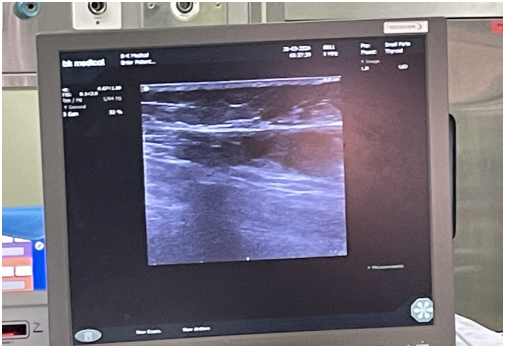

• 步骤2:B超引导下穿刺大隐静脉(膝关节附近),放置射频导管距离隐股交界2cm。

图片